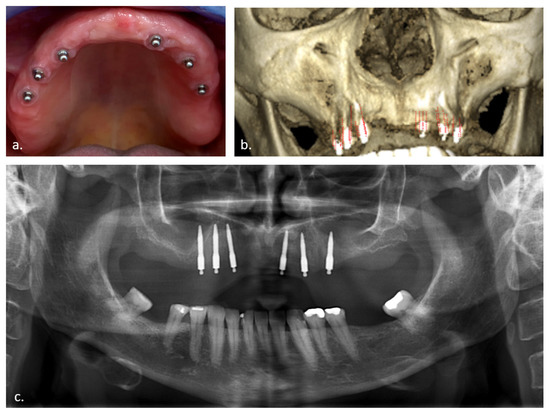

2.2. Radiological Examination